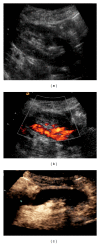

Renal transplantation is the treatment of choice for managing patients with end-stage kidney disease. Being submitted to a very serious surgical procedure, renal transplant recipients can only benefit from follow-up imaging and monitoring strategies. Ultrasound is considered as the principal imaging test in the evaluation of renal transplants. It is an easily applied bedside examination that can detect possible complications and guide further imaging or intervention. In this imaging review, we present essential information regarding the sonographic features of healthy renal transplants, detailing the surgical technique and how it affects the sonoanatomy. We focus on various complications that occur following renal transplantation and their sonographic features by reviewing pertinent literature sources and our own extensive imaging archives.